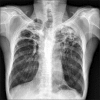

A 47-year old man visited our hospital because of purulent sputum for 3 months. Chest X-ray showed destruction of both the upper lungs, and bronchoscopy revealed inflammatory change with whitish plaque on the left main bronchus through upper division of the left upper lobe. Tracheobronchial aspergillosis (TBA) was finally diagnosed as a result of histologic and microbiologic examination. However, he went abroad without medication before the diagnosis was made and visited again 10 months later. Follow-up bronchoscopy showed complete regression of the previously noted endobronchial lesion. We describe this case to consider the role of antifungal treatment in immunocompetent hosts, as well as to discuss a rare condition; TBA resolved spontaneously.